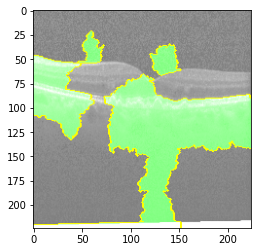

Original Image

Explanation B

Explanation C

Explanation D

GradCAM

Original Image

Explanation B

Explanation C

Explanation D

GradCAM

V MODEL EXPLANATION WITH XAI

Fig 6, 7, 8 and 9 depicts the visualization of correct predictions by our proposed CNN model where fig 6 is class CNV, fig 8 is class DME, fig 7 is DRUSEN and finally, fig 9 is NORMAL. Here the first photo in every class is the original image. The LIME map of our suggested model’s prediction is shown in image B whereas in image C the positive region is highlighted in specific sections on the original image. For Image D we have increased the number of features from 5 to 10 thus more regions have been predicted as the positive region which is highlighted in green. After increasing the features from 5 to 10, some of the regions are predicted wrongly. The red regions represent the output of incorrect prediction. The following image represents the Grad-CAM heatmap highlighting the regions with our model’s prediction.